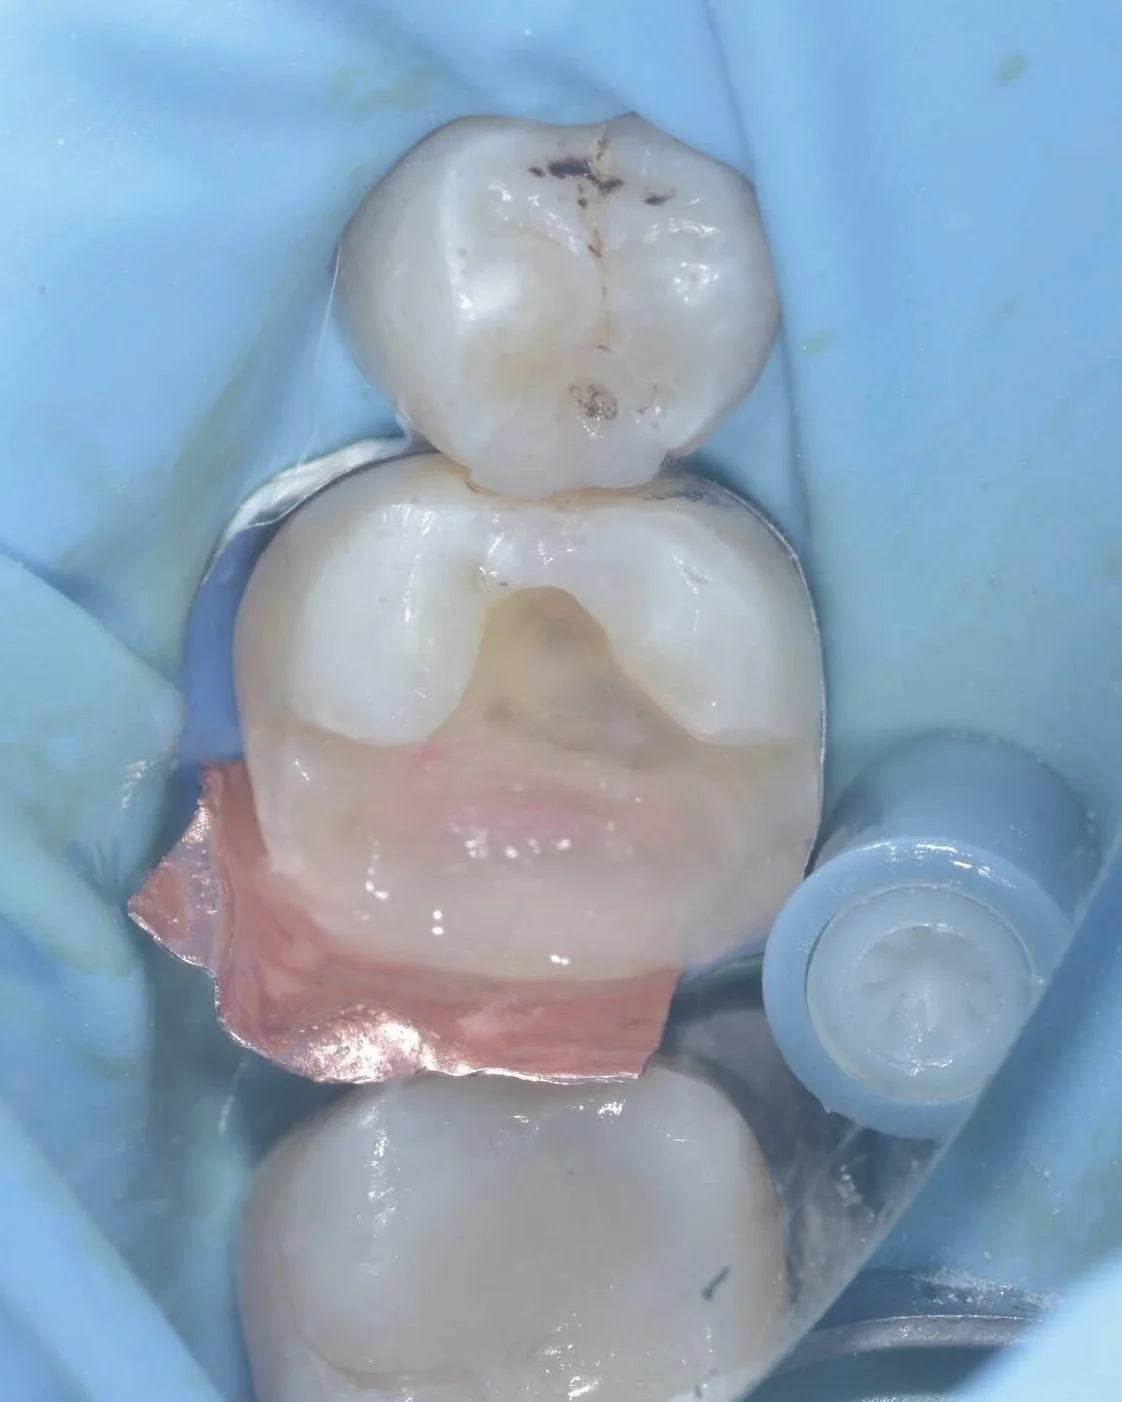

This case by Dr. Davey Alleman, DMD shows the process of removing caries around the pulp to create a caries-free peripheral seal zone.

This case by Dr. Davey Alleman, DMD shows the Six Lessons Approach steps from establishing caries removal endpoints to final cementation.